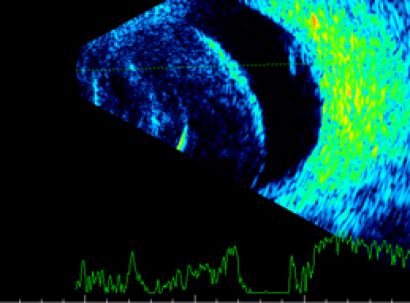

![]() |

| Дегенерация сетчатки | Друзы зрительного нерва |